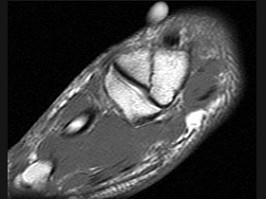

问题 女,25岁,扭伤后足中部痛,结合图像,最可能的诊断是 ( )

选项 A、中间楔状骨骨折 B、未见异常 C、外侧楔状骨骨折 D、足舟骨骨折 E、內侧楔状骨骨折

答案 E